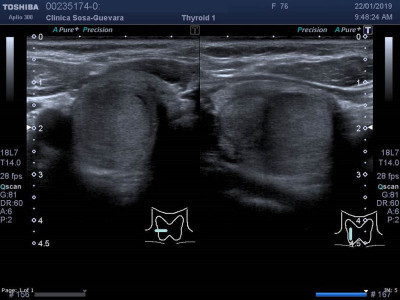

Ultrasonido de tiroides

Envíado por Clínica de Radiología y Ultrasonografía Sosa - Guevara